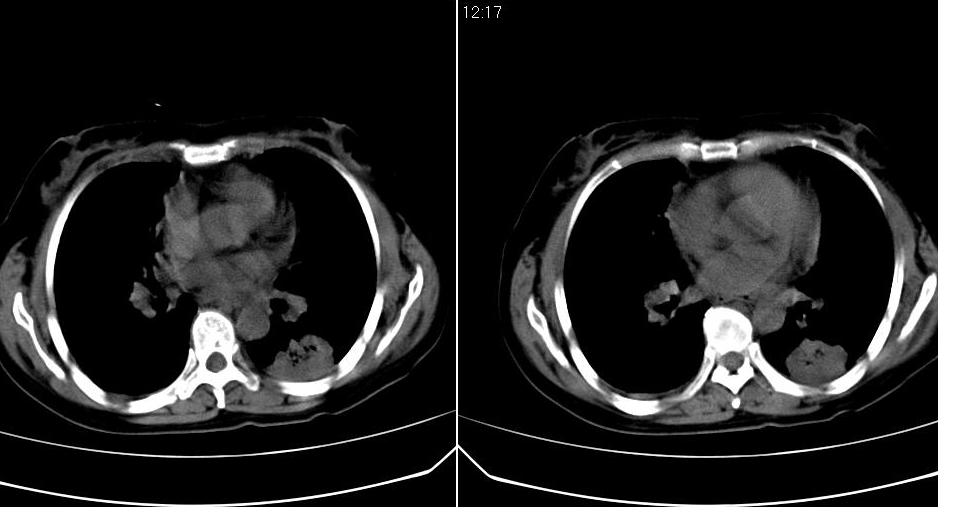

标题: CT16839:胸部CT平扫

女 50岁,在其他医院确诊肺癌.

肺癌并肺内及纵隔淋巴结转移

考虑 肺癌伴肺及纵隔转移,心包膜增厚